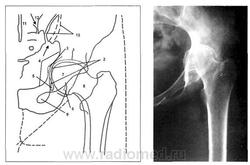

Зная нормальные взаимоотношения костей, образующих тазобедренный сустав, рассмотрим общие признаки наиболее характерных заболеваний - деформирующего артроза и артрита тазобедренного сустава. На рисунке 5 представлена типичная рентгенологическая картина деформирующего артроза тазобедренного сустава.

Рис. 5. Схема рентгенограммы тазобедренного сустава больной с деформирующим артрозом. Имеются следующие рентгенологические проявления заболевания сустава: медиальный квадрант головки располагается латеральнее «фигуры полумесяца»: нарушение линии Шентона (что формирует картину подвывиха головки); утолщение кортикального слоя и клювовидное разрастание крыши вертлужной впадины (оссификат хрящевой губы); деформация головки бедренной кости и сужение рентгенологической суставной щели (из руководства Майковой-Строгановой B.C., Рохлина Д.Г., 1957).

Основные признаки коксартроза:

• ненормальные соотношения между головкой бедренной кости и суставной впадиной;

• медиальный квадрант головки располагается латеральнее «фигуры полумесяца» (картина подвывиха);

• признаки нарушения нормальных соотношений протяженности крыши и ямки вертлужной впадины;

• крыша вертлужной впадины черепицеобразно нависает над ямкой, образуя подобие клюва;

• кортикальный слой в крыше вертлужной впадины значительно утолщен;

• рентгеновская суставная щель превышает норму и снижена в высоту за счет уменьшения хрящевого слоя.

Для коксартроза характерно также развитие оссификатов,которыекомпенсаторно увеличивают протяженность суставной щели, уменьшают нагрузку на единицу площади суставных поверхностей. Типичной локализаций оссификатов являются: наружный край вертлужной впадины на месте прикрепления хрящевой губы, нижний отдел в области вырезки вертлужной впадины и ее дно, нижний и верхний края головки бедренной кости. Выраженность дегенеративно-дистрофических изменений в тазобедренном суставе и их индексная оценка представлены в таблице.